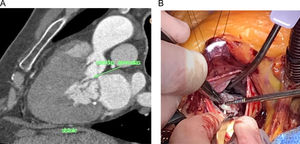

Reorientación de músculos papilares. El objetivo de este paso es conseguir el desplazamiento hacia posterior de la superficie de coaptación mitral. Al coaptar en un punto más lejano al septo, se reduce la posibilidad de que el velo anterior se desplace hacia el tracto de salida durante la contracción sistólica. La reorientación de la superficie de coaptación se obtuvo gracias al realineamiento en sentido posterior de los músculos papilares mediante una sutura no reabsorbibles de PTFE 4/0 apoyadas en 2 pledgets de 7mm. Se pasaron ambas agujas a través de todas las cabezas de ambos músculos papilares. En caso de observar posible fragilidad tisular (cabezas de pequeño tamaño, bífidas), se optó por atravesar con las agujas solo la cabeza más anterior y la más posterior, rodeando el resto. Durante la colocación de este punto se extremaron las precauciones para no interferir con ninguna cuerda tendinosa y se anudó ejerciendo la mínima tensión necesaria para aproximar entre ellos los papilares, sin estrangular ni seccionar las cabezas musculares2,6,8 (fig. 3).